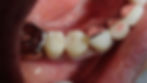

今回の方は右下前から3番目~5番目までを一度に治療しました。

写真上の左二つがCAD/CAM冠で一番右がレジン前装冠と言われる被せ物になります。

実際にお口の中につけたのがこちら。

上からの図がこちらです。

人工物感は否めませんが、少なくとも金属の被せ物よりは違和感は少ないと思います。